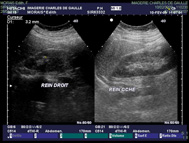

| L’examen est basé sur l’utilisation des ultrasons. |

| Une sonde placée au contact de la peau, émet des ultrasons qui arrivent au contact des organes et reçoit la réponse qui est transformée en image. |

| Tous les organes pleins peuvent être explorés en échographie : foie, vésicule, pancréas, reins, vésicule biliaire, vessie, utérus, ovaires, thyroïde, muscles, seins. |

| Pour l’échographie rénale, pelvienne, prostatique, il

faut avoir la vessie pleine. |